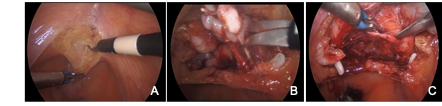

Debido a lo primitivo de los registros y comunicaciones de la época, la paternidad de la primera nefrectomía radical es controvertida. Las búsquedas muestran que la primera nefrectomía exitosa la realizó el cirujano alemán Gustav Simon en la Universidad de Heidelberg el año 1869. También hay testimonios que indican que el Dr. William Hingston, cirujano canadiense, en 1868 en el Hotel Dieu Hospital en Montreal, habría efectuado también una exitosa nefrectomía(16). Lo que sí está meridianamente claro es que 122 años después, en 1990, el Dr. Ralph Clayman en la Universidad de Washington (St. Louis), realizó la primera nefrectomía radical laparoscópica, la cual se transformó en la técnica estándar para la nefrectomía radical por cáncer(17,18). Esta cirugía puede efectuarse tanto por un acceso transperitoneal como retroperitoneal, dependiendo de las preferencias del cirujano o de las características particulares del paciente o tamaño del tumor. Cuando se realizan por el acceso transperitoneal, debe movilizarse ampliamente el colon derecho o izquierdo (incluyendo ángulos hepáticos y esplénicos), según corresponda, para extirpar en bloque la bolsa de Gerota y su contenido (Figura 20). En el lado derecho hay que hacer necesariamente una maniobra de Kocher (movilizar el duodeno) para acceder con comodidad al hilio renal (Figura 21).

Una manera segura y sencilla de acceder al hilio renal es disecar la Gerota en su extremo caudal, separándola de su íntima unión con el músculo psoas lumbar. Una vez ubicado el hilio, este debe ser disecado para controlar por separado arteria y vena. Usamos clips de ligadura de polímeros en forma rutinaria (ejemplos: Hem-o-LockTM, Teleflex), dos proximales y uno distal (Figura 22).

Se seccionan los vasos con tijera fría. En este punto se debe decidir preservar o no la glándula suprarrenal correspondiente o completar la disección del polo superior incluyendo la glándula en la bolsa de Gerota. En el lado izquierdo para preservar la glándula, se debe seccionar la vena renal entre la afluencia de la vena suprarrenal izquierda hacia la vena renal principal y el riñón, ubicar la cápsula renal y abandonar la glándula con la grasa que la rodea. En el lado derecho, posterior a ligar el hilio se debe ubicar la cápsula renal del polo superior dejando la glándula con la porción de grasa del polo superior que la rodea. Se completa la disección de la Gerota en forma roma. Por último se secciona el uréter y los vasos gonadales(19,20). Una vez liberada la pieza, se atrapa en una bolsa de PVC de 15 cm de diámetro y se extirpa por el sitio de Nyhus, previamente preparado (antes del pneumoperitoneo), marcando el sitio con un lápiz indeleble en la piel y disecando la fosa iliaca cuando la cirugía es retroperitoneal. Recomendamos hacer la marcación de este sitio antes de efectuar el pneumoperitoneo ya que, cambia la disposición anatómica con el abdomen insuflado. La ventaja del abordaje retroperitoneal es que se evita la disección de vísceras intraperitoneales. Como desventaja se tiene un campo quirúrgico más reducido.